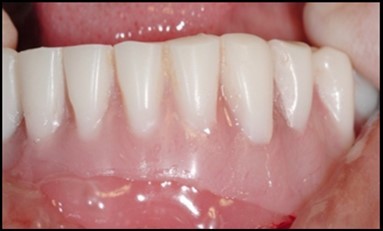

A transferable mark with an indelible pencil is placed on top of each ball abutment and old denture is seated to ideally determine the location for attachment housings. It is followed by preparation of recesses in the intaglio surface of the denture to accommodate the housings (Figure 7B). Lingual vent holes are made for escape of excess acrylic. Placement of nylon processing insert into each of the housings is done with insert seating tool. Figure 8 Seating of the attachment housing onto each ball type abutment is done (Figure 9). Undercuts are blocked out under the housing and soft tissue to prevent acrylic resin from locking the denture onto the abutment. Application of self curing acrylic is done into recessed area and around titanium housings for bonding of the housings to denture. Insertion of denture was done and guiding the patient into proper occlusion with the opposing arch. After the curing of acrylic, denture is removed. Excess acrylic is removed around the housings and lingual vent hole later it is polished (Figure 10). Replace nylon retention insert instead of processing insert into the housings. The insert must seat securely in place and be in level with the housings rim. Overdenture is seated over the ball abutments (Figure 11). Proper instructions have been given to the patient on insertion and removal of prosthesis (Figure 12). The patient was recalled at 1 week, 3 weeks, 3 months, 6 months follow up appointments.

Figure 11.View of denture after being cleaned and polished